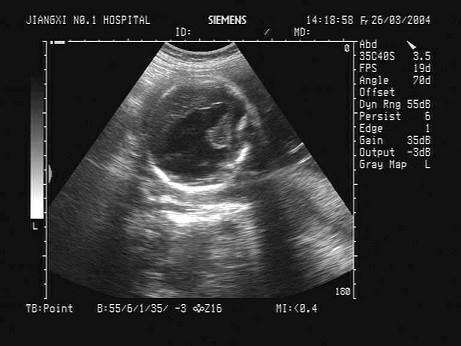

一孕妇,孕28周,根据胎儿头部B超声像图,最可能的诊断为?(?)A.胎儿脑积水B.无脑儿C.脑膜脑膨出D.正常胎儿E.透明隔囊肿

问题 一孕妇,孕28周,根据胎儿头部B超声像图,最可能的诊断为?(?)

选项 A.胎儿脑积水 B.无脑儿 C.脑膜脑膨出 D.正常胎儿 E.透明隔囊肿

答案 A